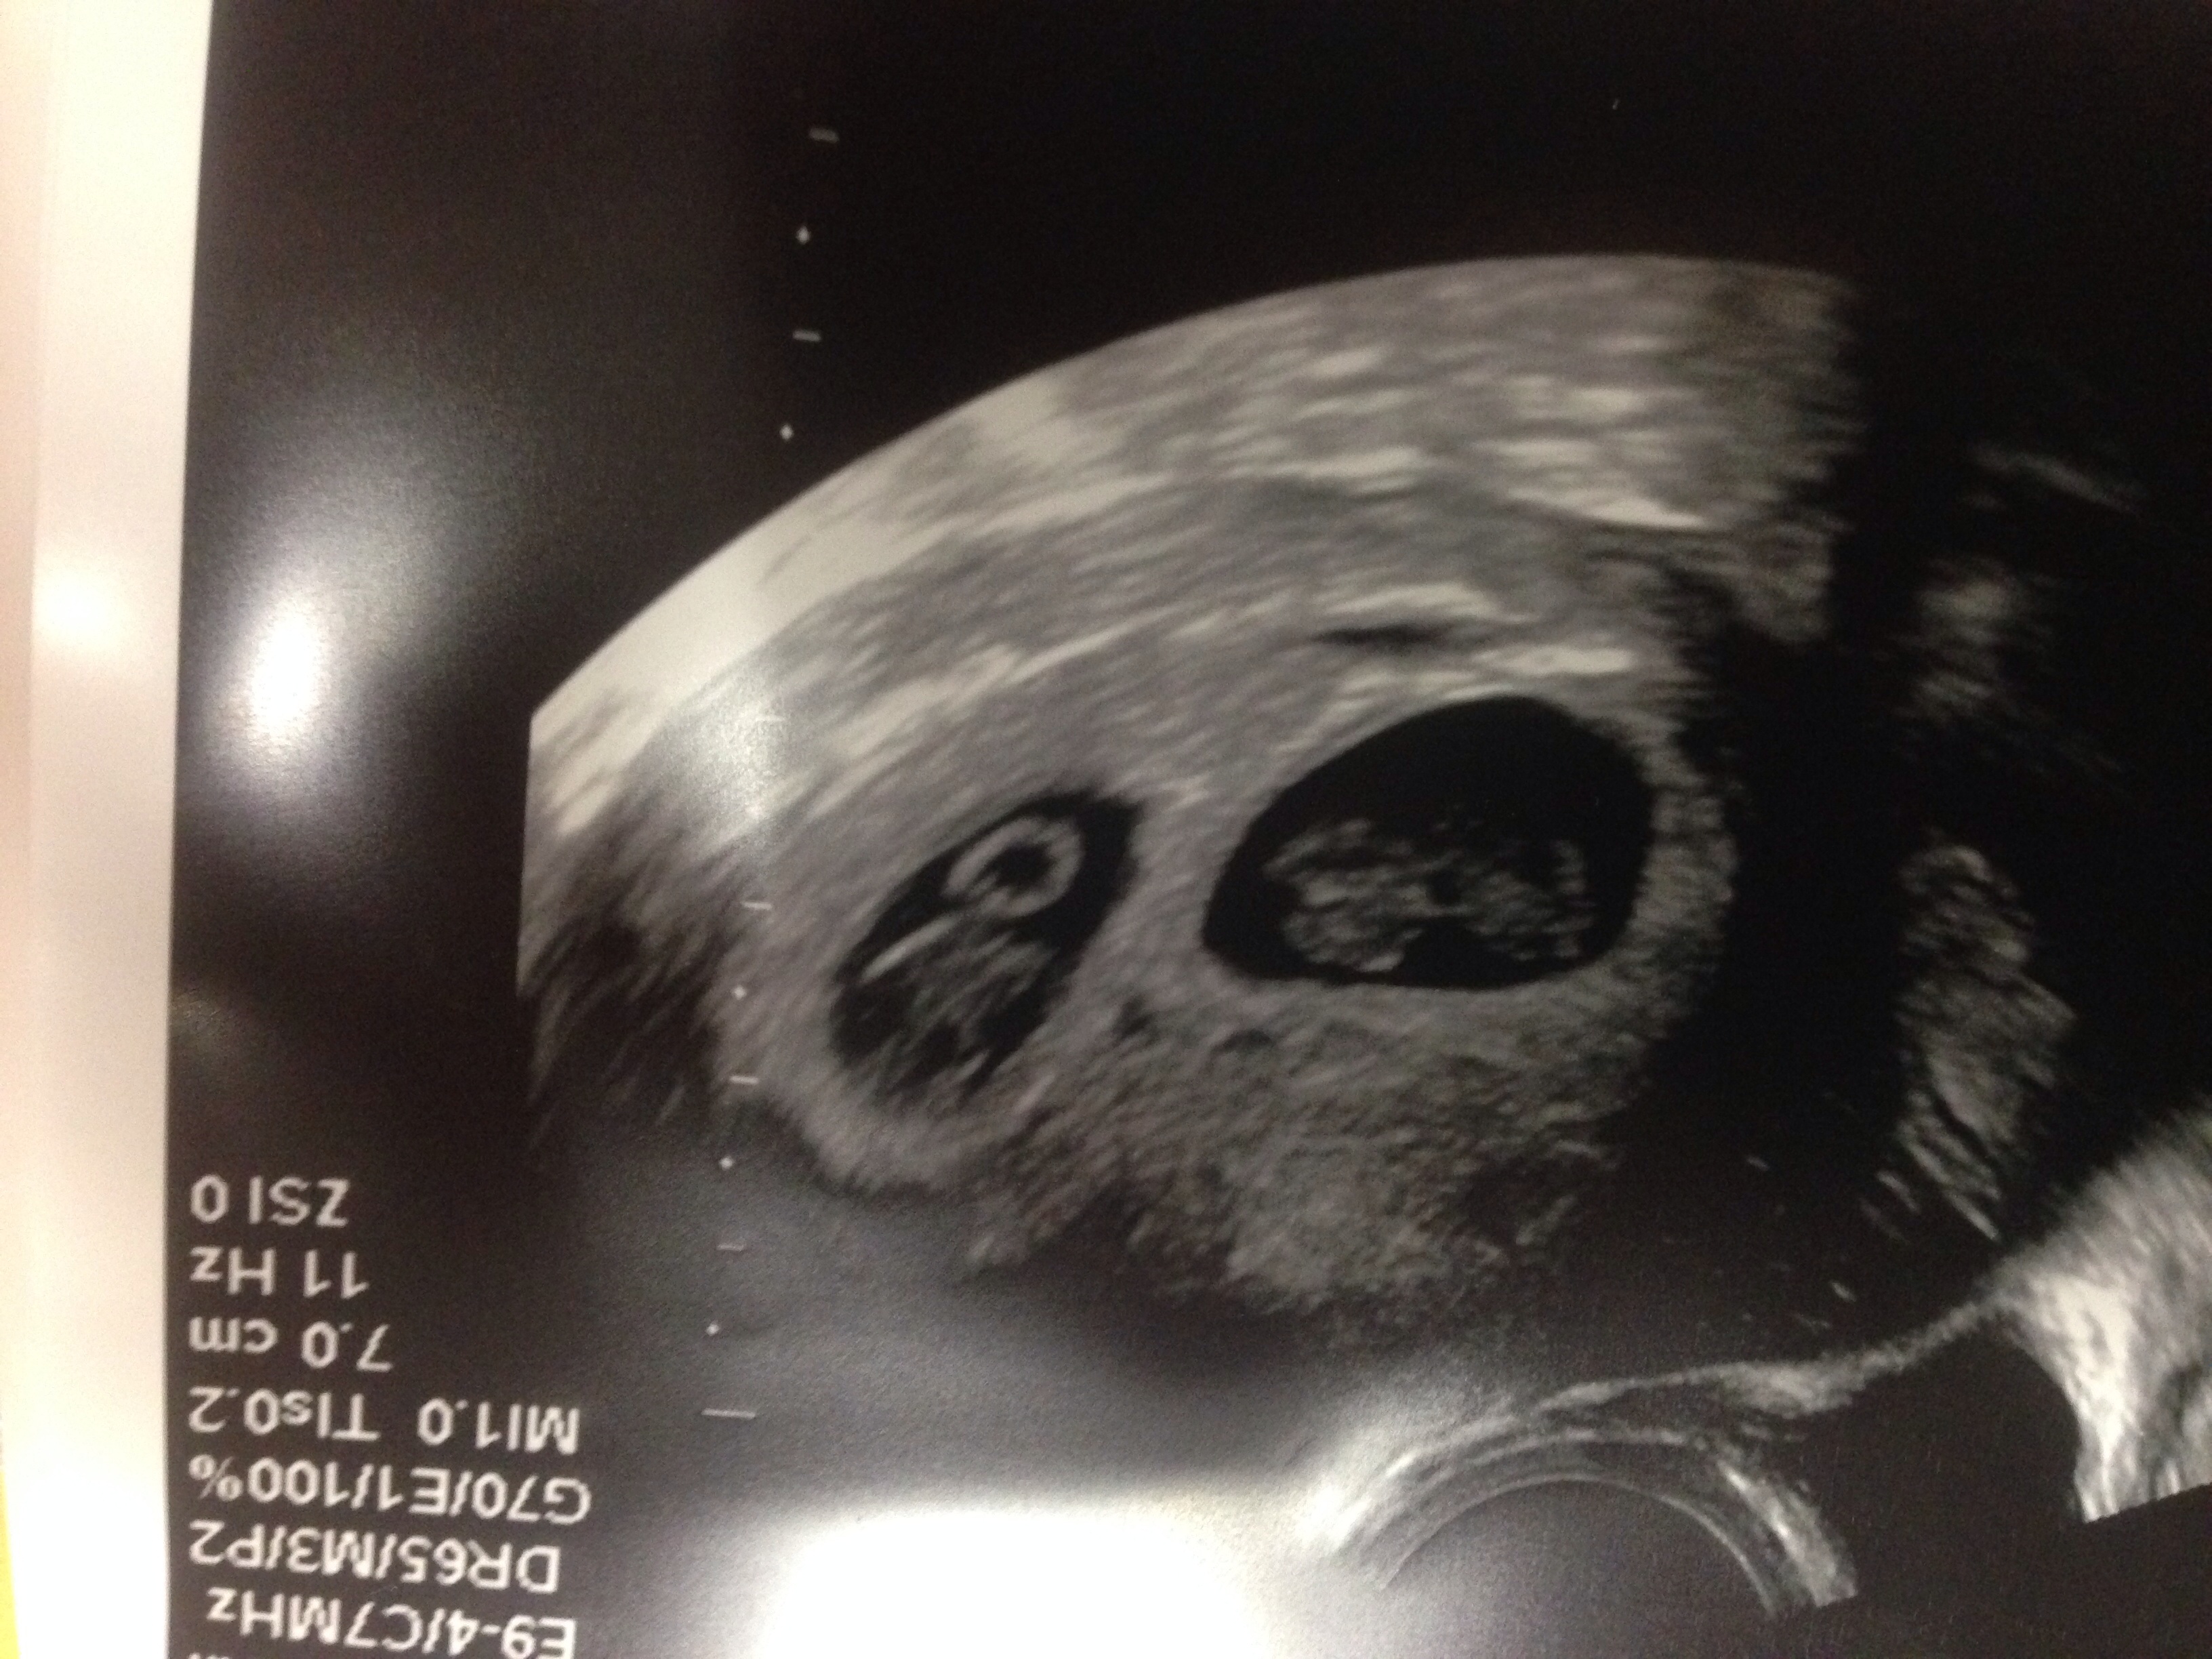

We went to our first appointment this morning. They confirmed a delivery date of 1/8/2014. All is well, but we found out that we are having twins! We are excited but the news is overwhelming as well!

Our first and second apparently ) I had an inkling but wasn't really thinking about it seriously. The first pregnancy test came back extremely bold and I tested early. I have been dreaming about a girl but keep thinking that it is a boy. Guess it could be both after all. Finally the weeks of all day nausea has been wearing.